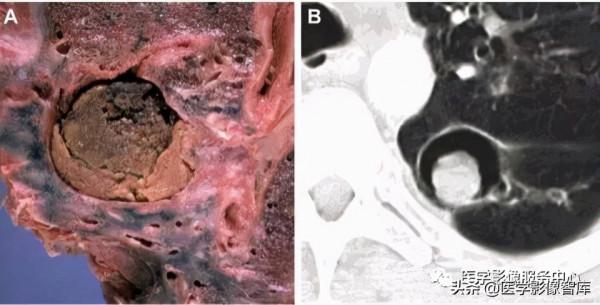

圖4.空⽓新⽉徵,表現為部分含⽓的新⽉狀透光區並不透光的實質部分

空⽓新⽉徵:空⽓新⽉徵被描述為⼀個完整或部分含⽓的新⽉狀透光區並不透光的實質部分(圖4),該徵象與侵襲性麴黴菌感染密切相關。麴黴菌菌絲侵⼊肺⾎管,引起動脈⾎栓形成、肺梗死和周圍出⾎。空⽓新⽉徵透光區是壞死中⼼與周圍不透光的出⾎組織分離的結果。臨床上,空⽓新⽉徵出現標誌著疾病的恢復階段,預示著良好的預後。Gefter等⼈的報告顯示,67%的急性⽩⾎病患者伴有空⽓新⽉徵,⽽沒有這種徵的患者存活率只有8%。空⽓新⽉徵在其他如肺結核、肺膿腫、⽀⽓管肺癌等疾病中也可⻅到。這個徵象理論上與下⾯描述的Monod徵是有區別的。

圖5. A和B為Monod徵

Monod徵:由Pesle和Monod在1954年提出指的是在⼀個已經存在的肺空腔中,圍繞著⼀個真菌球的空⽓,它落在了肺的⼀個與重⼒相關的位置,這是⼀個重要的標誌,CT掃描可以在不同的位置進⾏,以引起腔內腫塊的移動,有助於區分“先前存在的腔內的腫 塊”,如圖5A, 5B。它與空⽓新⽉徵交替使⽤,雖然理論上⼆者有⼀定的差別,但是也普遍被國內外學者接受,⼆者均在麴菌病中多⻅,預後良好。

圖6 暈徵,A,B和C為侵襲性麴菌病患者的暈徵⼤體病理標本和CT表現

暈徵:暈徵是CT掃描肺部的⼀個實性肺結節,周圍有環形磨玻璃樣陰影(GGO)。典型的常⻅於侵襲性真菌感染,如侵襲性肺麴黴病(圖6A-C)和免疫缺陷患者的肺粘膜真菌病。組織病理學上,中央的結節為梗死的病灶,伴周圍的GGO。其他⾮感染性原因包括⾁芽腫病伴多⾎管炎、澱粉樣變、結節病、腺癌和轉移性癌。